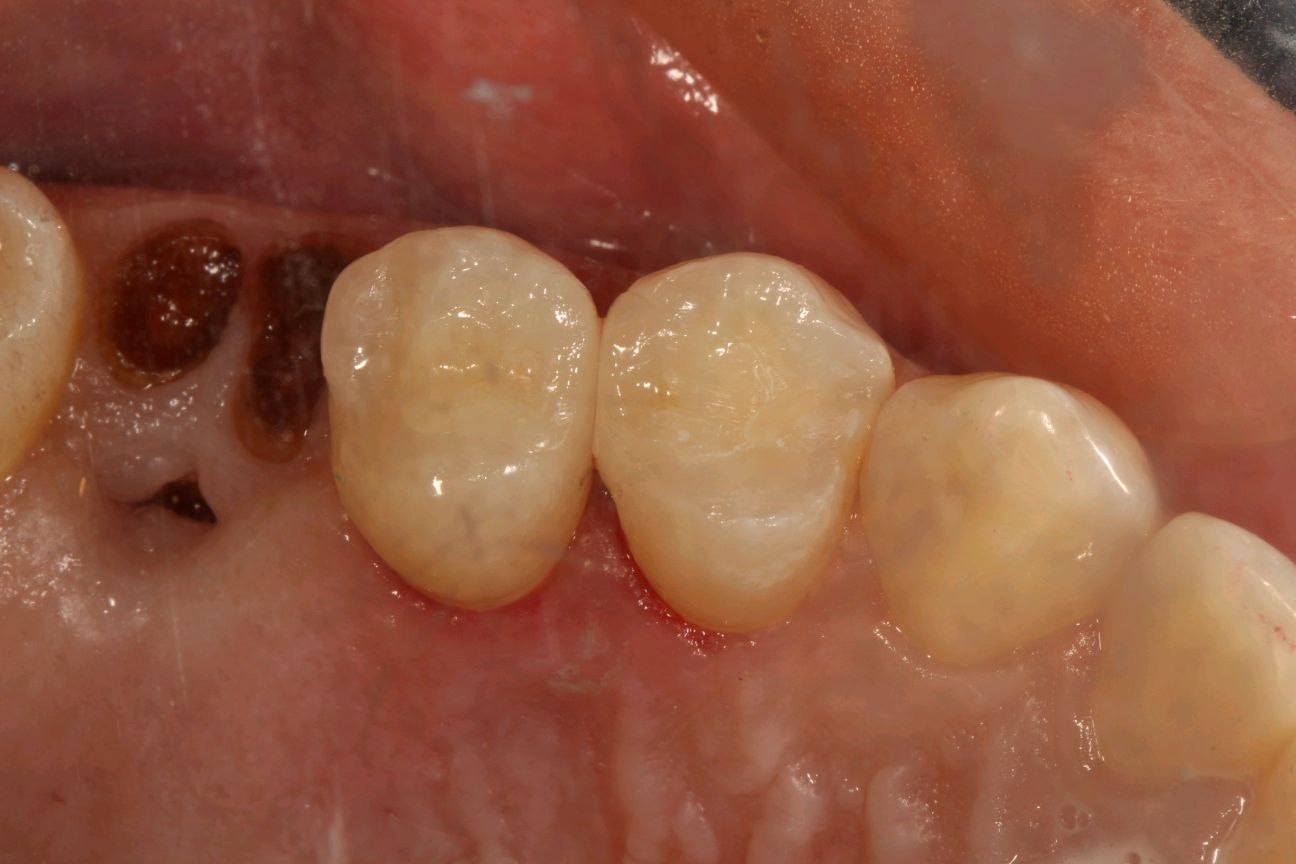

患者女,34岁,24、25邻面龋坏。经患者同意去腐备洞行嵌体修复。后通过德国 CEREC 技术扫描后,数据分析精准有效,"量身定做"专属于自己的修复体。患者当天即可配戴,既保证了边缘的密合性,还确保了色泽和形态的美观。患者不会有很强的异物感和咬合的不适。大大提高了工作的效率,也节省了患者的时间。

术后